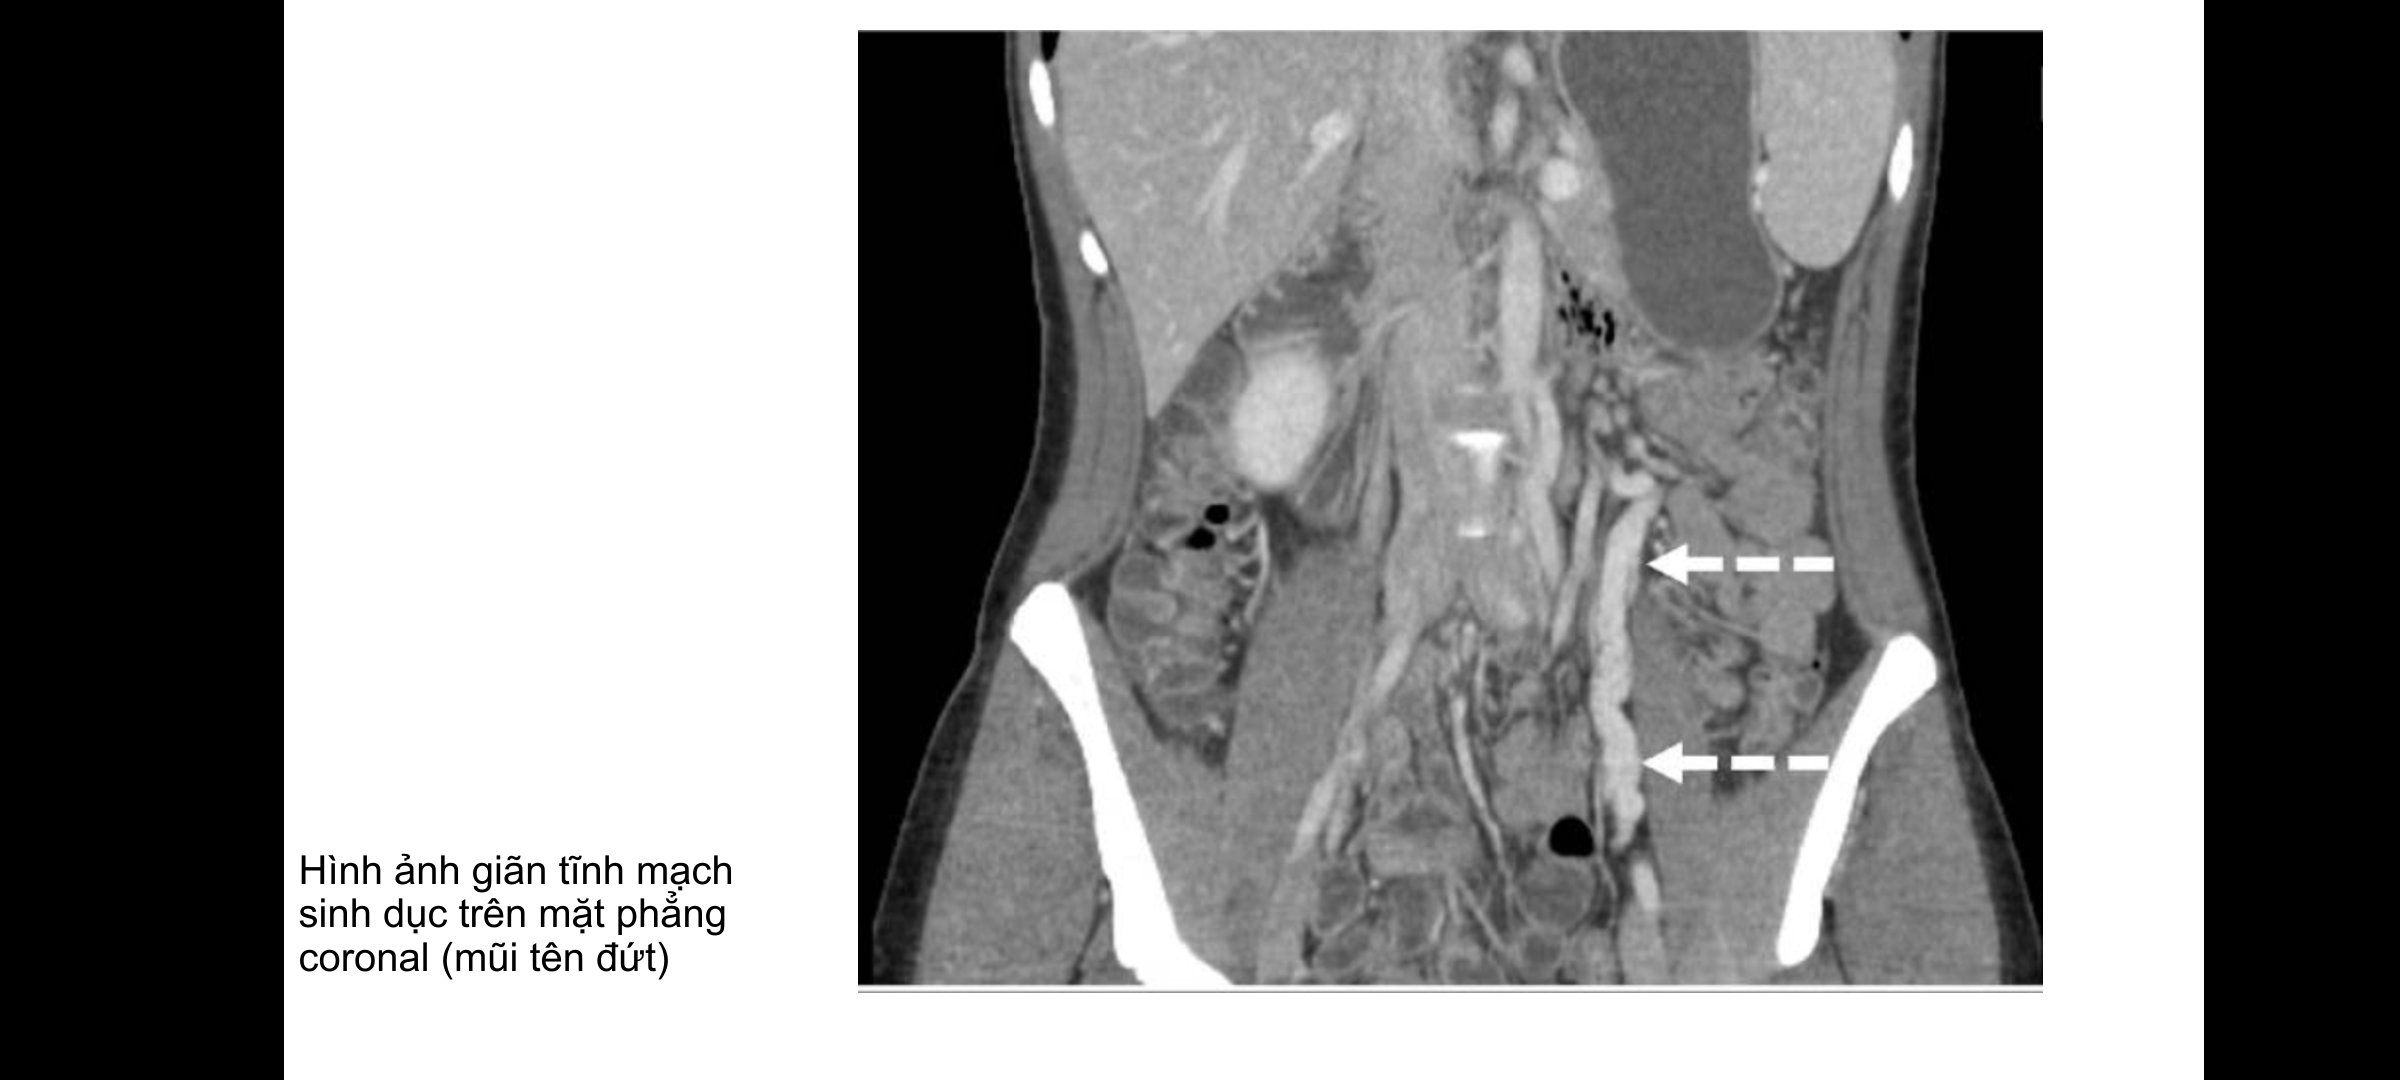

Để chẩn đoán hội chứng xung huyết vùng chậu, bác sĩ thường dựa vào các triệu chứng đau kéo dài trên 6 tháng và buồng trứng căng đau khi thăm khám, ở nam giới là triệu chứng đau, sưng vùng trên bìu và giảm khả năng sinh sản. Ngoài việc dựa vào các dấu hiệu triệu chứng, người bệnh có thể được chỉ định các phương pháp như siêu âm, cắt lớp vi tính, cộng hưởng từ để chẩn đoán.